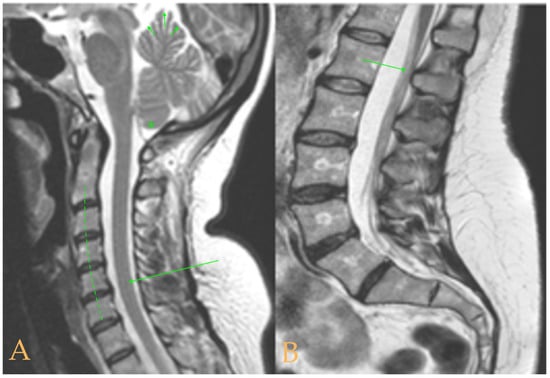

The MRI showed a descent of the cerebellar tonsils, increased supracerebral space, and micro lacunae in the bilateral white matter and the left basal ganglia. Upper cervical kyphosis and straightening in the lower levels. Surgical arthrodesis at C4-C5 and C5-C6. Cervical, thoracic and lumbar protrusions. Ischemia and oedema in the cervical and thoracic spinal cord. Slight cervical rotoscoliosis. Disc protrusions: T7-8, T11-L1, L2-L3-L4, and disc herniation L4-L5. Loss of the lumbar lordosis. Conus medullaris at the level of the middle third of the L1 vertebra (Figure 2). The X-ray images of the entire spine showed levoconvex thoracolumbar scoliosis of 21°, dysmetria of the lower extremities with shortening of the right lower extremity by 10 mm, with respect to the level of the hip, and 99 mm at the level of the iliac crests, 16° cervical lordosis, 49° thoracic kyphosis, and 59° lumbar lordosis.

Figure 2. Imaging of patient 2. A: Image suggestive of spinal cord ischemia (arrows), impaction of the cerebellar tonsils (star), and straightening of the cervical spine (interrupted line); B: straightening of the upper part of the lumbar spine (interrupted line) and conus medullaris at the level of the L2L3 disc space (arrow); and C: brain MRI with micro lacunae in the white matter (arrows).